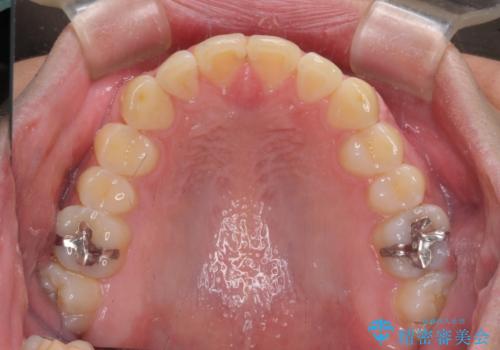

- 上下前歯のデコボコを気にして来院された患者様です。

前歯のデコボコ以外に左側の奥歯の咬み合わせに問題がありましたが、価格を抑え、短期間で気になる前歯を治したいとのことでした。

こちらの患者様は、事前のシミュレーションにより、インビザライン・ライトでは前歯のデコボコを解消しきれないことが分かったため、通常のインビザライン(コンプリヘンシブパッケージ)での治療が必要となりました。

しかし、費用面や期間で悩んでいらっしゃったため、左側臼歯の問題は解決せずに前歯のデコボコのみを改善するシミュレーションを作成し、治療を行うこととしました。

写真より左側臼歯の咬合がタイトではないことが分かりますが、こちらは保定期間に徐々に咬合させていくこととしました。